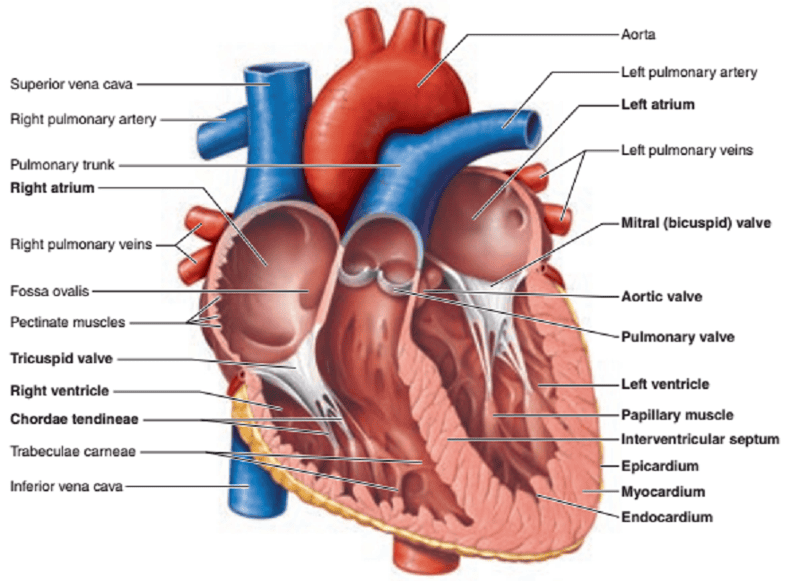

Name the missing parts.

Heart external anterior view

Heart frontal section

Frontal section